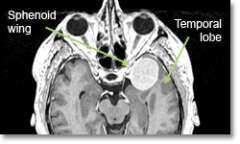

Location - Sphenoid Ridge

Common Symptoms - Eye-bulging, decreased vision, paralysis of eye movement, seizures, memory difficulty, personality change, headache.